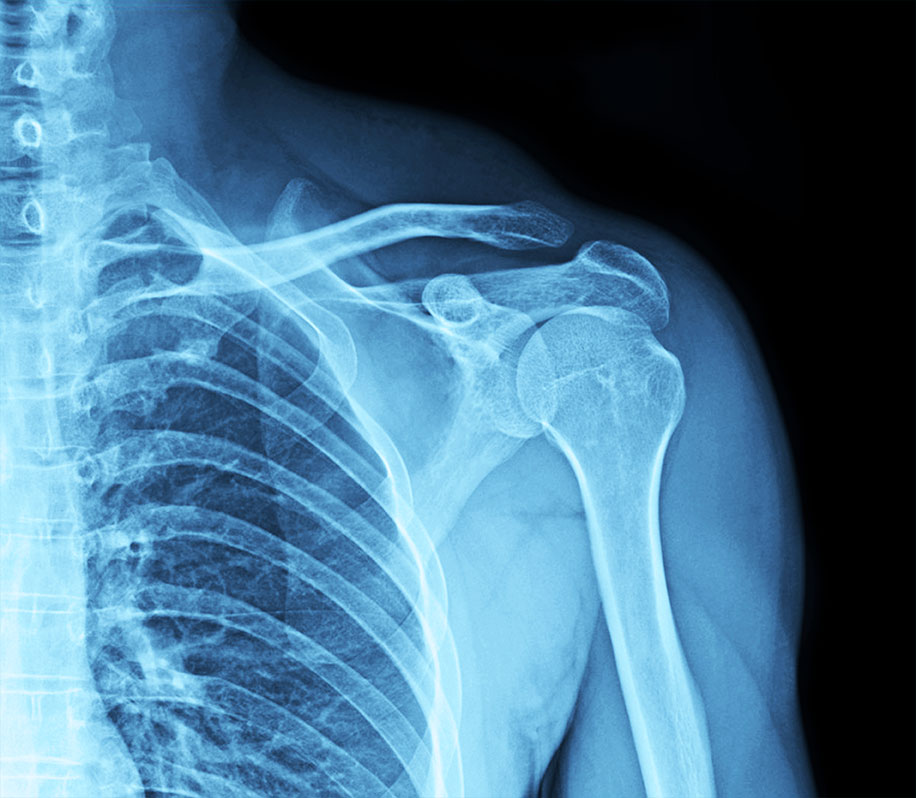

2. OSTEOPOROSIS AND BONE HEALTH

Estrogen is crucial for bone density maintenance. Its decline accelerates bone loss, increasing the risk of osteoporosis and fractures, particularly in the hips, spine, and wrists.

Bone Density Scan (DEXA Scan): Measures bone mineral density and assesses fracture risk.

Vitamin D and Calcium Levels: Ensures adequate levels for bone strength. Parathyroid Hormone (PTH) and Thyroid Function Tests: These help assess calcium metabolism and overall bone health.